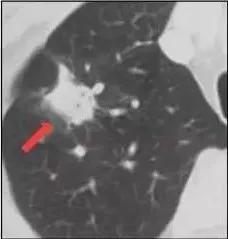

3.实性结节

结节长相:肺内圆形或类圆形密度增高影,病变密度足以掩盖其中走行的血管和支气管。

产生原因:一般实性肺结节恶性可能性很高,多是由肿瘤导致。但是否是恶性,还需要结合大小等因素综合判断。